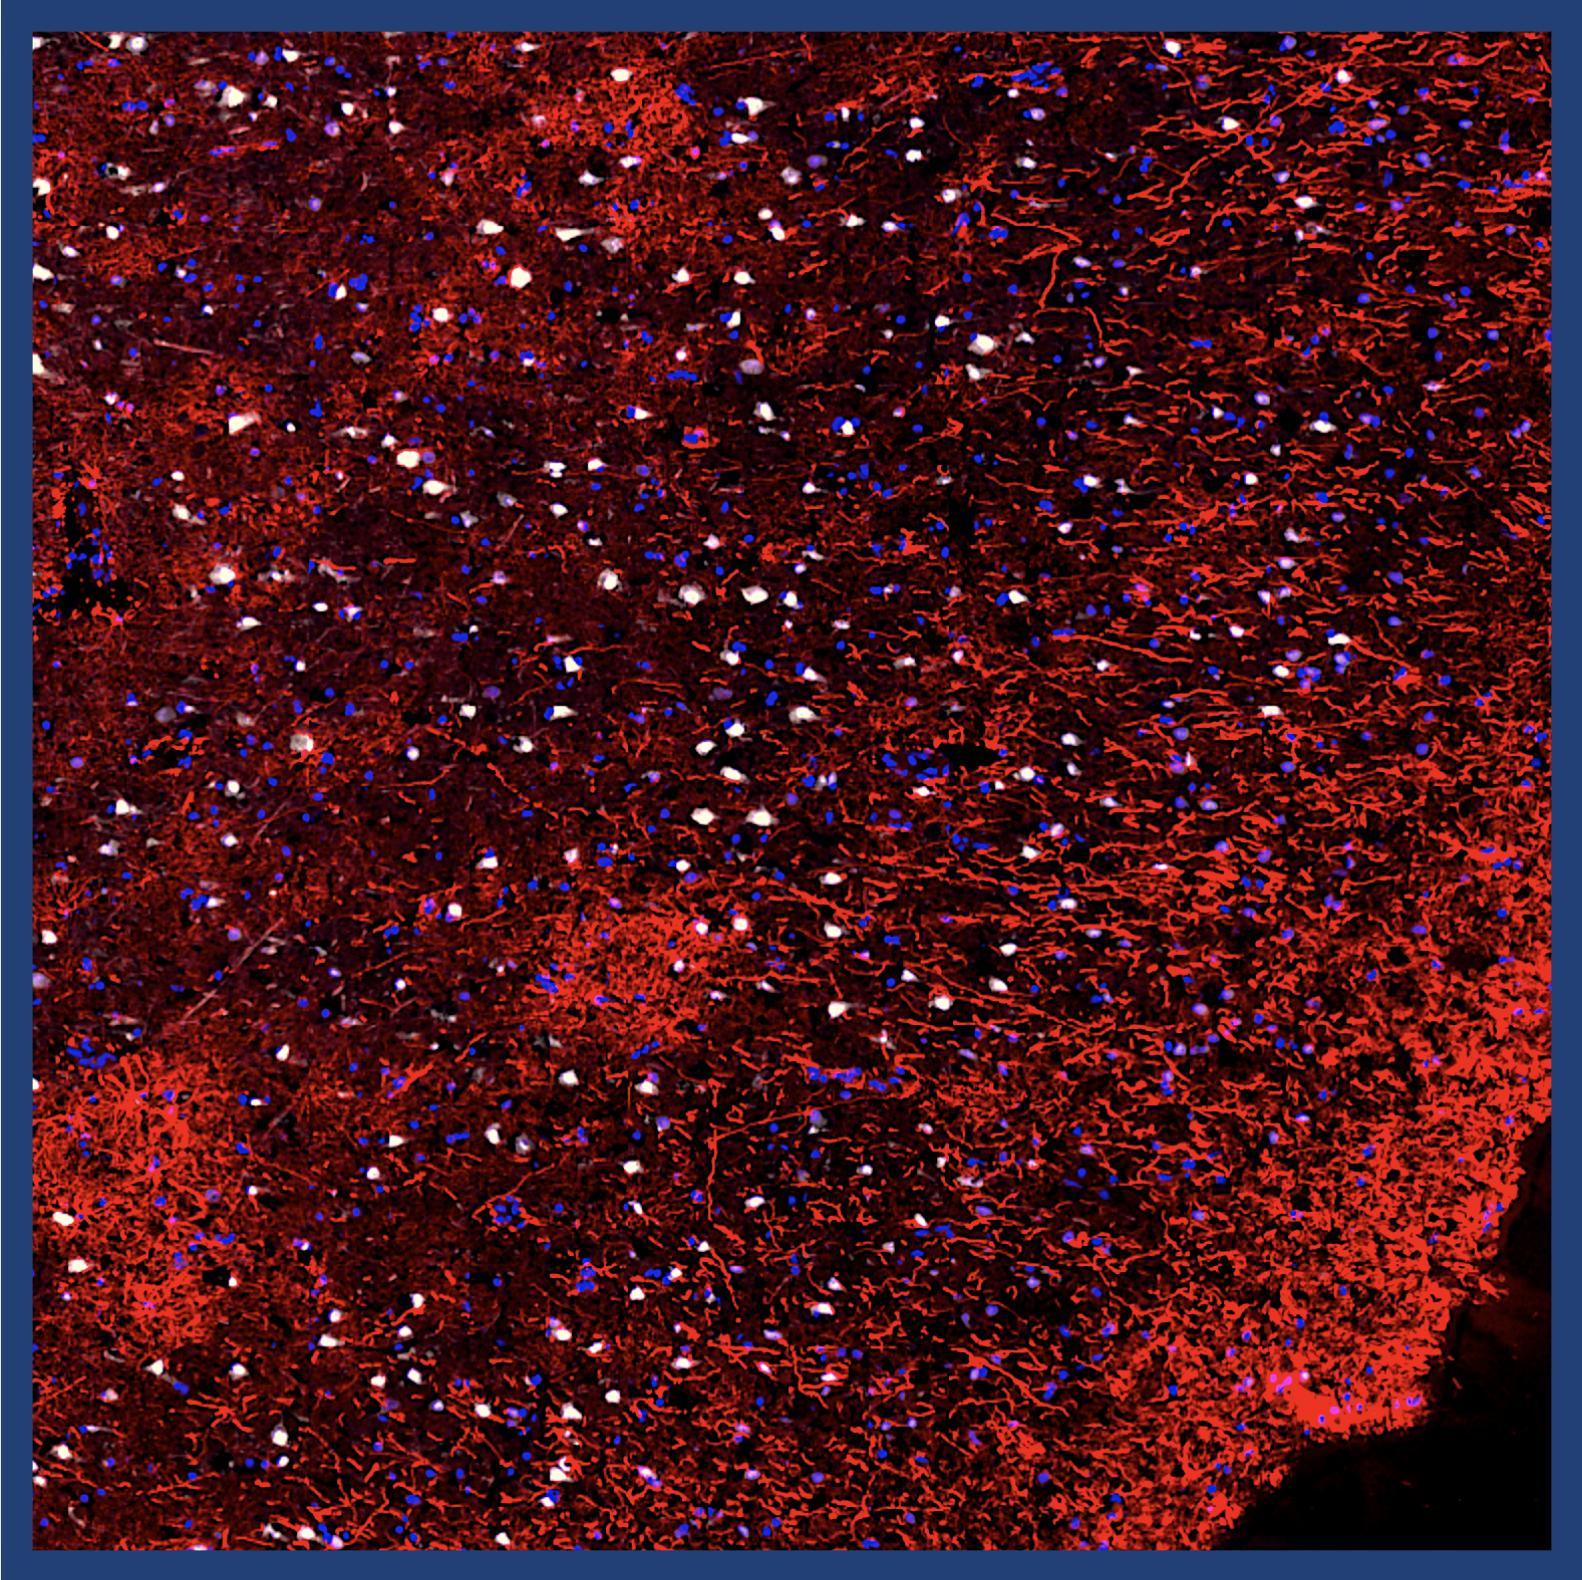

Neurobiological mechanisms of opioid addiction

The ongoing opioid epidemic has triggered our interest to investigate the molecular mechanisms underlying opioid use disorder (OUD). Using rodent models of drug self-administration and advanced molecular biology techniques, we aim to uncover the neurobiological processes driving OUD. Our ultimate goal is to identify molecular targets to develop effective therapeutics and contribute to combating the opioid crisis.